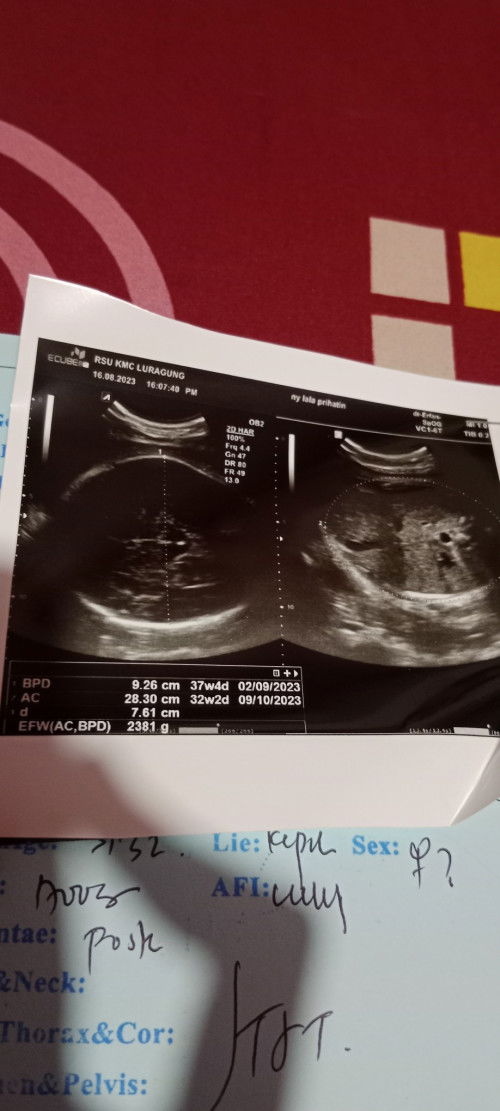

Kalo dilihat dari hari pertama haid terakhir (HPHT) harusnya bunda masuk Minggu ke berapa ya? Kalo hasil usgnya lumayan jauh ya usia perkiraan berdasarkan lingkar perut sama lingkar kepala. Biasanya sama bidanku dijelaskan dua usia tersebut dirata2kan, kalau berdasarkan foto USG bunda jadi 34-35 ya. Tapi emang paling sesuai minta penjelasan dr dokter/bidan yg handle bunda yaaa sebelum selesai kontrol. Sehat selalu bunda ☺️

kok jauh banget ya ukuran lingkaran kepala sama lingkaran perut. sampai 5 minggu bedanya. waktu itu pernah liat vt dr wiku di tiktok, untuk uk lihat bagian yg solid seperti tulang, kemungkinan ya bunda uk 37w . terus bbjnya kecil jadi lingkar perut janin cuma sekian itu. coba konsul aja sama spog, deh barangkali ada problem sama si kecil.

nanya ko lumayan detail dan dokter bilang normal semua, aku cm bingung ac sma bpd nya knp jauh gtu aku ga nanya karna gatau tau tau pas hasil usg dah keluar

37 minggu 4 hari bun.. klo dibaca dr USG